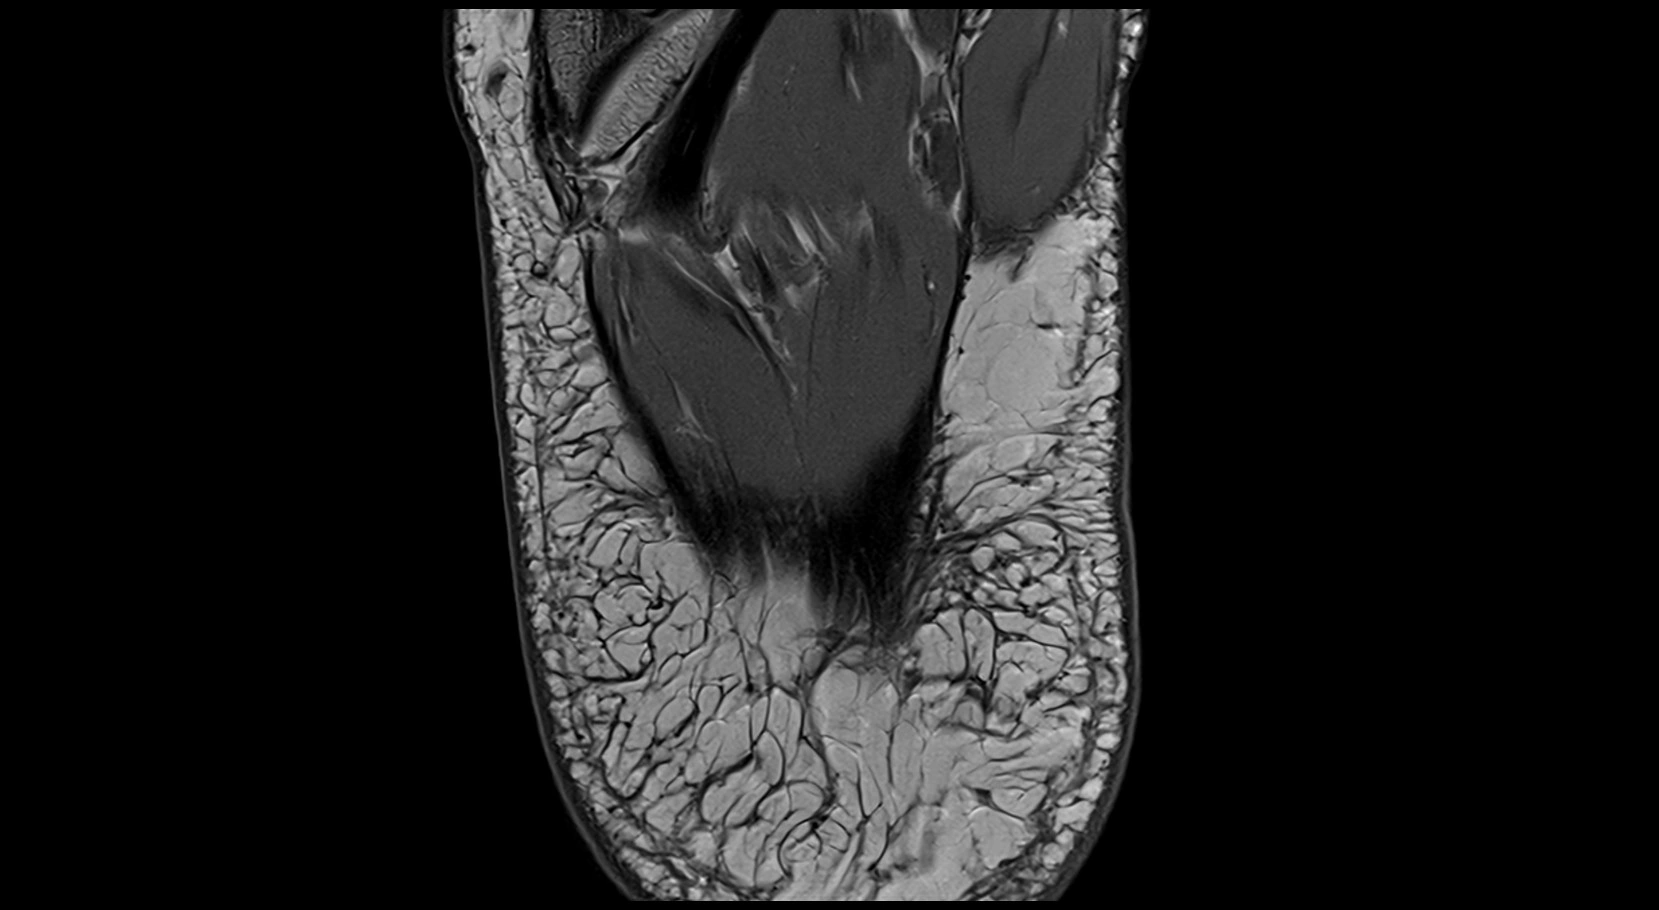

MRI image

image